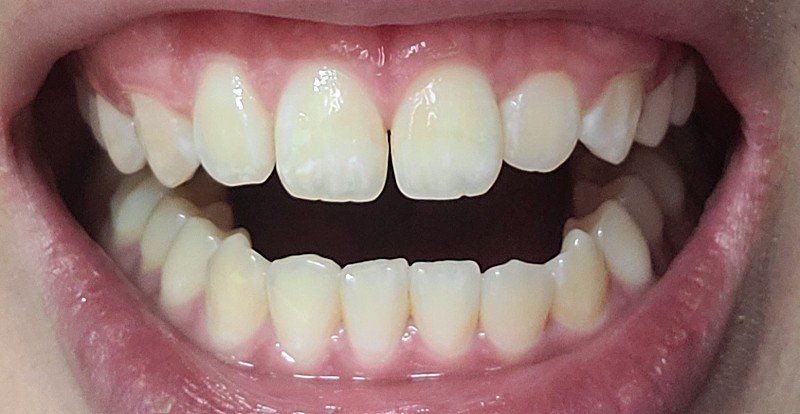

예전에는 안그랬던것같은데 오랜만에 치과가서 치아를보니 앞니치아가 살짝 벌어졌더라고요

□저처럼 성인이여도 앞니치아가 살다보면 자연적으로 벌어질수있나요?

1. 나이가 들면 앞쪽으로 치아가 쏠리거나 힘을 받게 되어 치열이 변화할 수 있습니다. 따라서 앞니에도 영향이 있을 수 있습니다.

교합에 의해서 앞니에 교합간섭이 일어나게 되면 앞니가 벌어지는 경우가 있습니다.

성인의 경우에도 치아가 벌어질 수 있습니다. 또한 혀로 앞니를 계속 의도적으로 밀면 더 벌어질 수 있습니다.

자연적으로 벌어질수 있습니다.

치아의 마모가 일어나고 치아들이 미세하게 이동하면서 치열이 틀어지게 되는 치아배열의 노화